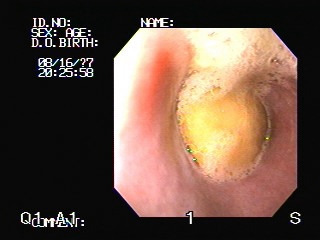

강아지가 이물을 먹어서 병원에 오는 사례

2.jpg

1.jpg

<좌> 식도에 사과가 걸린 경우 내시경 사진, <우> 식도에 개껌이 걸린 경우 방사선 사진

사진출처 : 24시 센트럴 동물 메디컬센터

아동기는 호기심이 왕성하고 에너지가 넘치는 시기라고 말씀드렸는데요,

이 때문에 먹어서는 안 되는 이물을 먹거나 급하게 먹다가 식도에 걸려서 병원에 오는 사례가 많습니다.

먹어서는 안 되는 이물 외에도 간식 등의 음식이 식도에 걸려서 급하게 병원을 찾는 경우도 많아요.

음식이 식도에 걸리면 호흡곤란, *연하곤란 등의 증상이 발생하게 됩니다.

식도에 음식이 걸린 경우, 2-3일이 지나면 식도에 염증이 심해져 이물을 제거한 후에도

*식도협착 으로 만성 구토가 발생할 수 있습니다.

먹어도 되는 음식이라고 해서 안심할 수 없고 주의가 필요합니다.